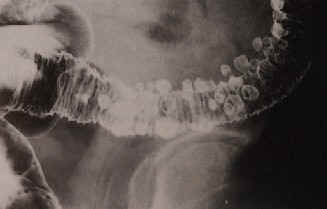

- Computertomographie - virtuelle Coloskopie/Colographie